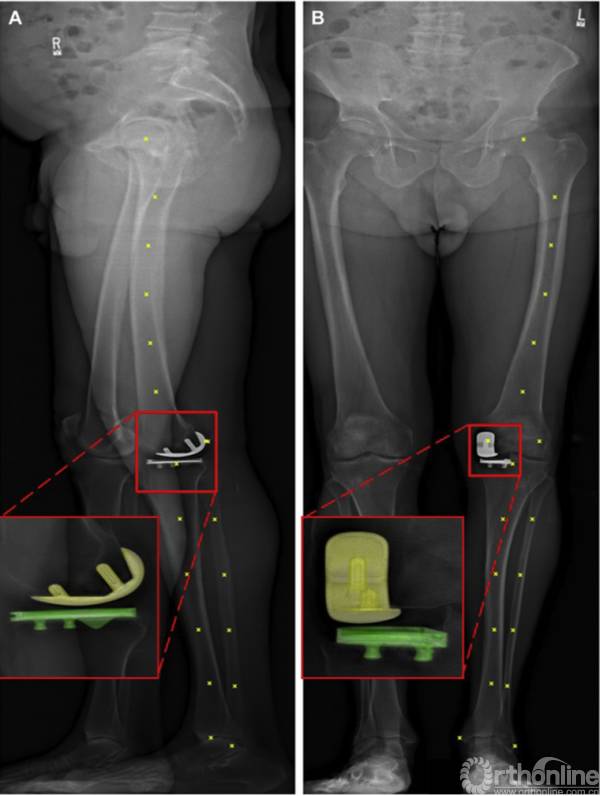

所有患者使用双平面放射摄影术(EOS Imaging,Biospacemed,Paris,France)在平均随访时间为49.2个月(范围6.7-119.1)下在承重站立位置成像。我们在本研究中使用双平面放射摄影作为计算机断层扫描(CT)扫描的替代3D测量。双平面放射线照相系统先前已被验证用于测量TKA的部件对准,全髋关节置换术和下肢对准,并且它具有大大减少的电离辐射暴露的优点和能够执行全身体在承重,站立位置下的扫描。

2.2使用EOS 3维匹配方法

每个患者位于用于图像采集的双平面放射摄影系统的视野中,两个膝盖轻微弯曲以避免由处于站立位置的对侧膝盖的图像遮挡(图1)。双平面X线片上的Bony标志用于重建股骨和胫骨解剖坐标系统(图1A和B)。使用AP上的最下部和后侧髁点和侧向X线片选择内侧和外侧股骨后髁(图1A和B)。从双平面射线照相投影的交叉点重建骨标记的3D位置。使用通过两个长骨轴的中心的最佳拟合3D线确定股骨和胫骨的长轴和近侧/远侧轴。股骨前/后轴平行于经髁线和股骨长轴的叉积。对于胫骨,腓骨轴中心和胫骨轴中心与穿过它们各自的重心的3D平面拟合。确定最佳拟合平面的法线向量和胫骨长轴的叉积作为连接胫骨和腓骨的重心的线。事后施加42°内部轴向旋转偏移以将内侧/外侧轴线移动到后胫骨髁轴线。

图1

来自制造商的UKA计算机辅助设计模型被导入到MATLAB(MathWork,Natick,MA)中定制的虚拟EOS成像环境中。使用先前发表的优化程序来找到用于确定UKA分量位置的最佳位置。我们对相对于用骨性标记构建的解剖学坐标系统执行3D UKA部件对准的测量,参考先前发表的用于冠状和矢状股骨/胫骨部件的对准、先前发表的2D UKA射线照相标准以及用于轴向胫骨部件旋转测量。中性分量旋转定义为0°(垂直于先前定义的对应的股骨和胫骨解剖轴)。